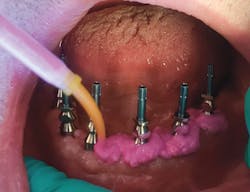

I seat the direct pickup copings hand-tight onto the multiunit abutment, syringe a light-body polyvinyl siloxane (PVS) around the coping, and then fill the MiraTray with medium or heavy-body PVS as well (figure 5). Seating the MiraTray is what makes it indispensable in the full-arch impression. The long screws of the direct pickup coping poke through the material on the tray, allowing easy access for the screw while keeping the material confined (figure 6). The tray is kept in place as the impression material sets up. Once it is ready, each of the copings must be unscrewed until the impression is released from the multiunits.